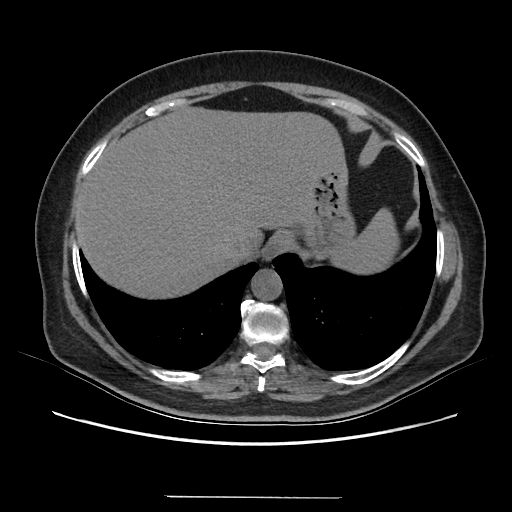

Original VENOUS CT scan

No window - Raw intensity values